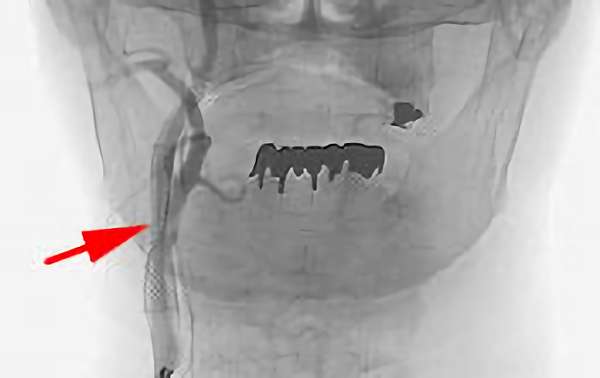

No.113 手術中